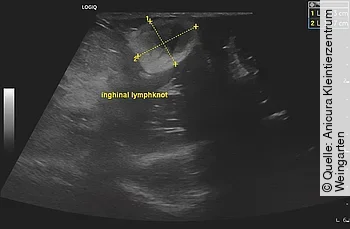

Abdominaler Ultraschall

Bei der Ultraschalluntersuchung des wachen Patienten in Rückenlage mit einem linearen 12 MHZ Schallkopf wurde eine generalisierte Vergrößerung des mesenterialen Lymphknotens festgestellt ([Abb. 2] und [3]). Die Darmschlingen zeigten eine gute Peristaltik mit einer fokalen Verdickung des Dünndarms und Zäkums. Kaudal der leicht gefüllten Harnblase wurde eine geringgradige Menge freie Flüssigkeit festgestellt. Beide Nieren wiesen eine gute Abgrenzung zwischen Kortex und Medulla auf. Die Milz zeigte eine mittelgradige Vergrößerung und das Parenchym war mit multiplen rundförmigen und hypoechogenen Herden versetzt, ca. 1x1 cm im Durchmesser. Die Leber stellte sich geringgradig vergrößert dar und zeigte abgerundete Leberlappenspitzen.

Auch im Ultraschall wurde im Inguinalbereich eine hypoechogene, rundförmige Struktur mit ca. 1,5 × 2 cm Durchmesser festgestellt und als Lymphknoten klassifiziert. Der Patient wurde daraufhin mit Alfaxan Multidose (Fa. Jurox) in einer Dosierung von 4 mg/kg i. v. sediert und es wurden Feinnadelaspirationen des Lymphknotens sowie von Milz, Leber und dem mesenterialen Lymphknoten durchgeführt.